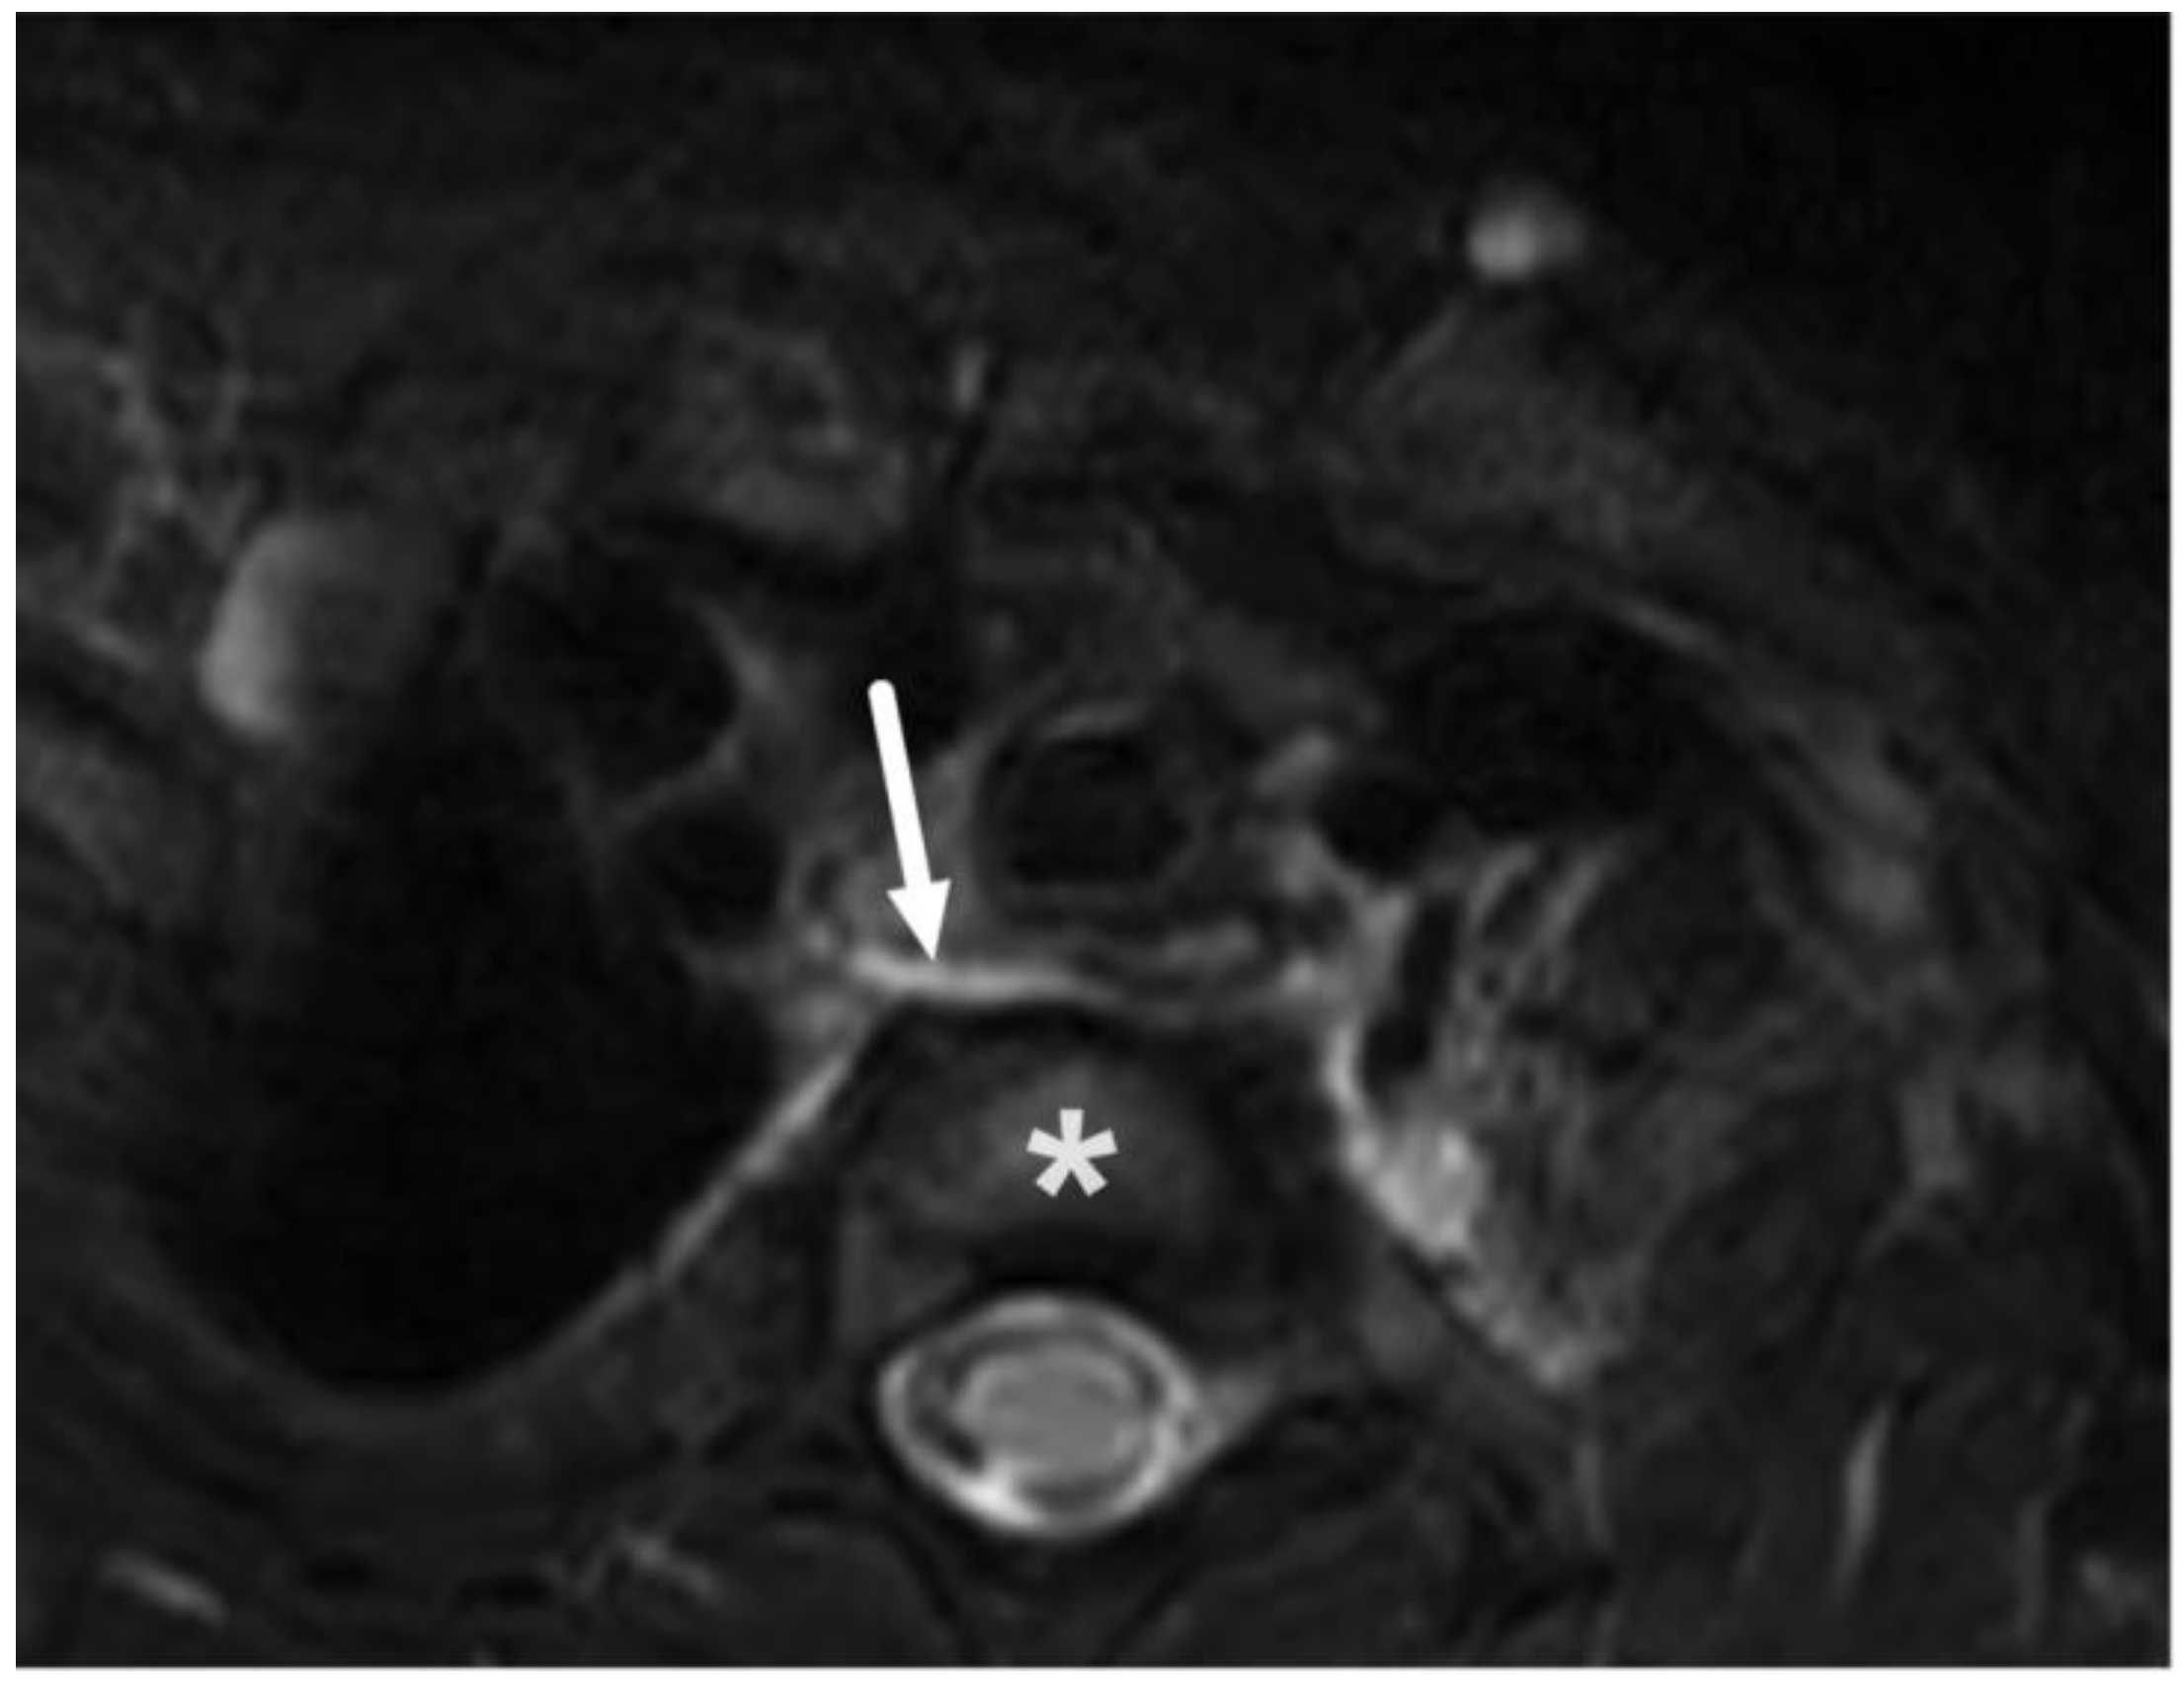

3.2. Terminology of Pathology

3.3. Edema Patterns